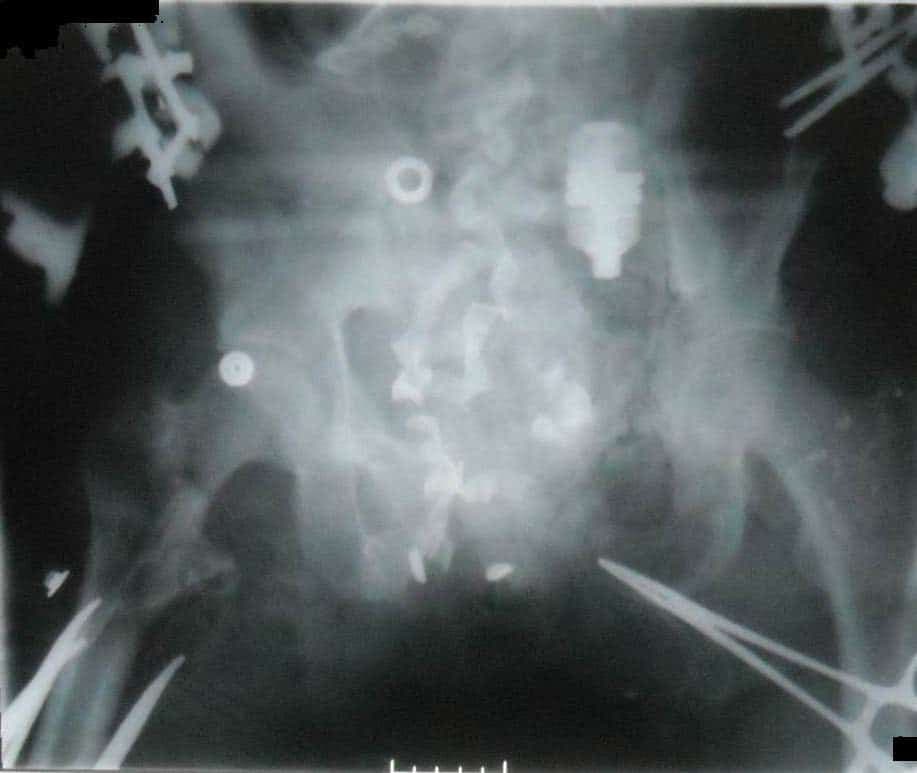

Найскладніші випадки включають відкриті переломи тазового кільця і ділянки навколо кульшової западини (Зобр. 2) та зміщення, пов’язані з тяжкими травмами промежини. Початкове ортопедичне реанімаційне втручання передбачає забезпечення достатнього контролю кровотечі з кінцівки за допомогою джгутів. Після початку інфузійної реанімації у пацієнтів часто починається кровотеча

Зобр. 2. Відкриті переломи тазового кільця і ділянки навколо кульшової западини

Зобр. 3. Той самий пацієнт після зовнішньої фіксації таза

Ампутація з атиповими ротаційними клаптями має набагато більше переваг порівняно з гільйотинною або відкритою круговою ампутацією. Слід докласти зусиль для збереження здорових тканин для закриття клаптем, навіть якщо доводиться виконувати атиповий ротаційний клапоть при відсутності або пошкодженні тканин для традиційного клаптя. При потребі краще виконувати стабілізацію тазового кільця шляхом зовнішньої фіксації (Зобр. 3 вище) замість тривалого використання затискачів з огляду на близькість до відкритих ран і необхідність послідовного висічення. Доцільно використовувати стержні для передньо-верхньої клубової ості / гребеня клубової кістки або передньо-нижньої клубової ості, причому останній вид стержня забезпечує найбільший контроль редукції, але його встановлення має здійснювати досвідчений хірург під рентгеноскопічним контролем.